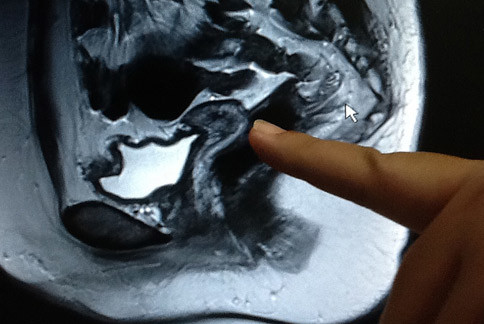

彰市雙十年華女子卵巢扭三圈